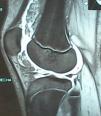

RMN de la rodilla derecha: pequeño quiste de Baker en la cara medial del hueco poplíteo, y moderado derrame articular en el receso suprarrotuliano. En el seno del derrame se observó un marcado engrosamiento sinovial que da imágenes de aspecto digitiforme o polipoide, que ocupaban el receso suprarrotuliano, la grasa de Hoffa y la parte adyacente a los ligamentos cruzados y meniscos. Estas formaciones tenían una señal igual a la grasa. Tras la administración de contraste iv se produjo un realce marcado de la sinovial que rodea a las lesiones polipoides. Esta imagen es diagnóstica de lipoma arborescens (fig. 1).